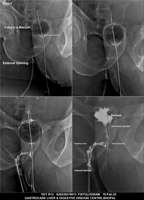

Section: FISTULOGRAM Total: 8 images

BaM Enteroclysis Loopogram BaE Fistulogram Urethrogram HSG